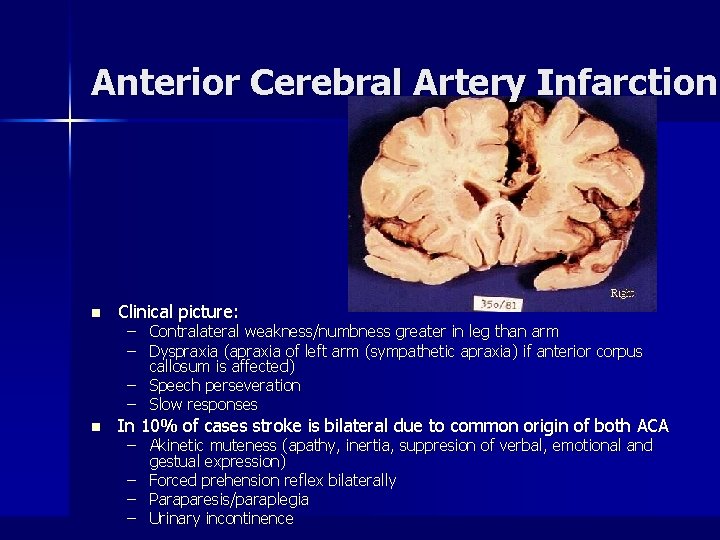

Anterior Cerebral Artery Infarction n Clinical picture: n In 10% of cases stroke is bilateral due to common origin of both ACA – Contralateral weakness/numbness greater in leg than arm – Dyspraxia (apraxia of left arm (sympathetic apraxia) if anterior corpus callosum is affected) – Speech perseveration – Slow responses – Akinetic muteness (apathy, inertia, suppresion of verbal, emotional and gestual expression) – Forced prehension reflex bilaterally – Paraparesis/paraplegia – Urinary incontinence